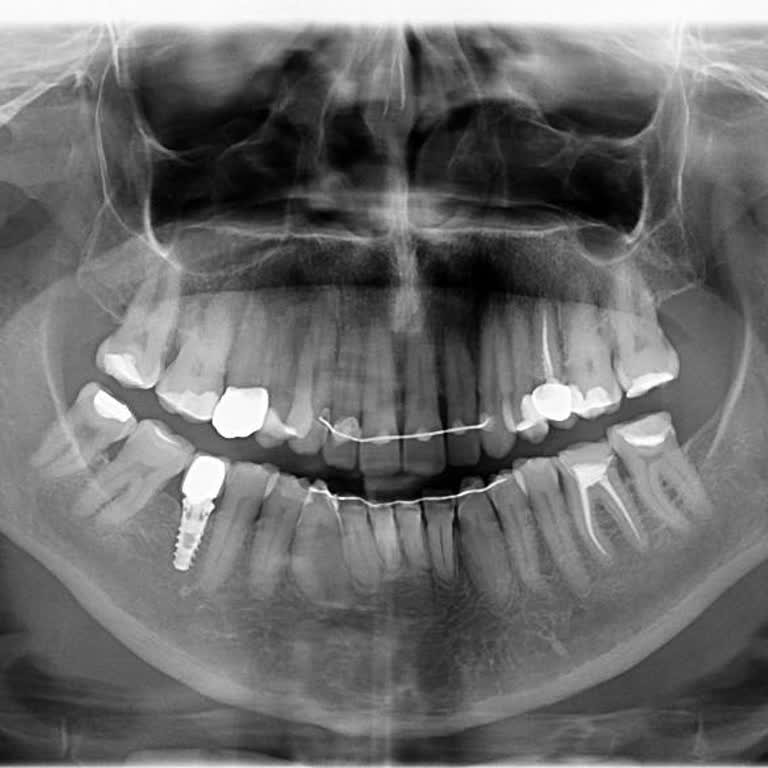

2 Kez ortodonti tedavisi yaptırdığım Diş Dr. Özge Özbilgen Utku maddi manevi kayba uğratmıştır. 25 sene öncesi tel taktırdım, dişlerim geri döndü daha sonra üst dişlerime başka bir doktor tel taktı ondan çok memnun kaldım. Özge hanım da 2022 yılında alt dişlerime tekrar tel taktı tedavi sonrası reta...